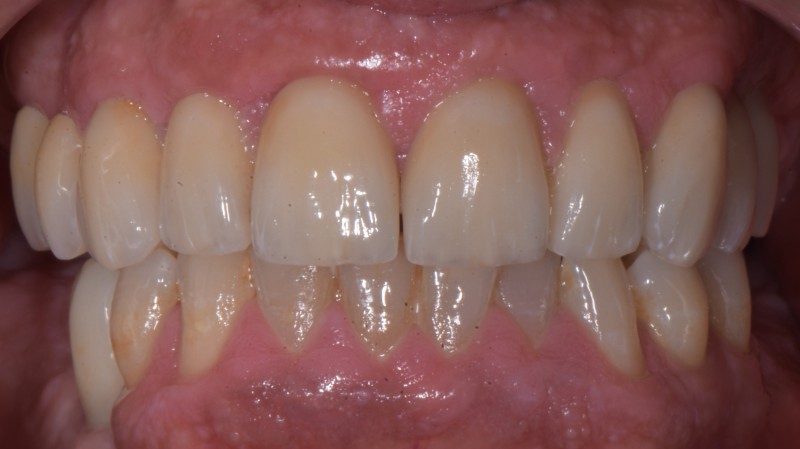

confronto visivo

Prima e Dopo il Trattamento

Trascina il cursore per confrontare il risultato ottenuto

Dopo il trattamento Prima del trattamento